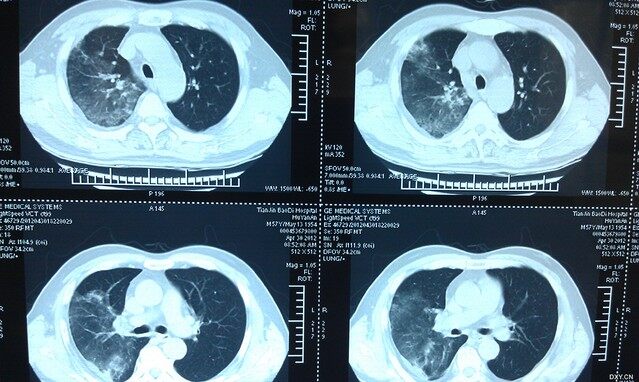

肺炎,作为一种常见的呼吸系统疾病,其发病率和影响力在全球范围内均不容忽视,随着医学研究的深入和病毒变异的多样性,肺炎的症状和表现也呈现出新的变化和特点,从古代的瘟疫到现代的新型冠状病毒性肺炎,肺炎的演变历程充满了挑战与突破,本文将详细探讨肺炎的最新症状及变化,并回顾其背景、重要事件、影响及其在特定领域或时代中的地位。

近年来,随着病毒的不断变异,肺炎的症状也呈现出多样化、复杂化的趋势,除了常见的发热、咳嗽、呼吸困难等典型症状外,一些新型病毒引发的肺炎还可能出现以下最新症状: